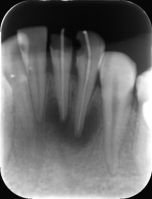

正常患者牙齿片

3.牙片分为几种?

常见X线片一般分为曲面断层片和根尖片,有些特殊情况还需要拍CBCT。具体需要拍哪种片子,根据每个人的牙齿情况不同会有所区别。